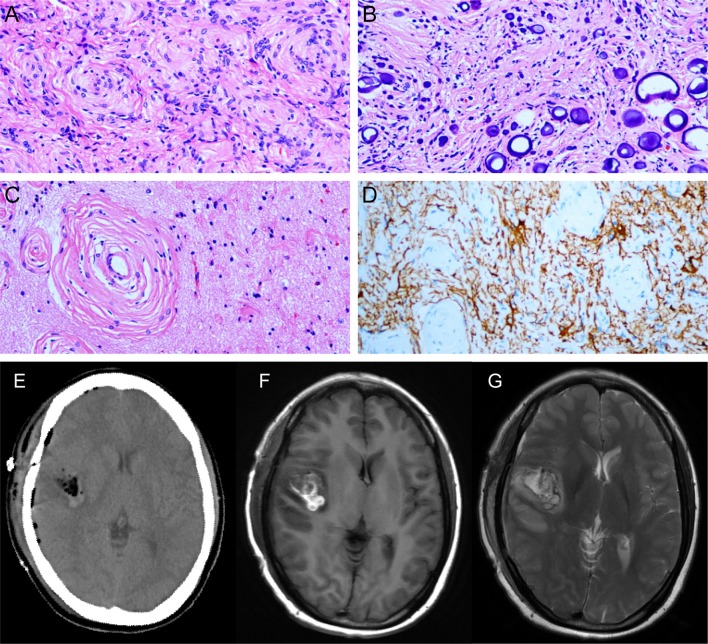

With this provisional diagnosis, the patient was referred for surgical management and underwent a right temporal craniotomy for gross total resection of the tumor and for seizure control. Upon opening the dura and separating the Sylvian fissure, a gray-white lesion (diameter, about 25*20 mm) was observed. It had a relatively elastic consistency and the mass partially invading the brain parenchyma of the insula, was densely adhered to the branches of the medial cerebral artery (MCA), and had partial calcification. Intraoperatively, despite careful micro-dissection, the MCA perforators were mildly damaged. Ultimately, several surgical specimens of the excised tumor were sent for histopathological analysis. Postoperatively, the results of histopathological examinations revealed a World Health Organization (WHO) grade II meningioma of atypical type (Figures 2A–D). Immunohistochemical examinations revealed negative immunoreactivity for Ki-67, progesterone receptor, p53, epithelial membrane antigen, and positive immunoreactivity for vimentin, and somatostatin receptor 2.

Figure 2.

(A) The tumor tissue arranged in swirl structure to form the meningeal corpuscle. (B) Psammoma bodies. (C) The meningeal corpuscles invade normal brain tissue. (D) GFAP staining show brain tissue (+) and meningeal corpuscles (-). Postoperative CT (E) and MRI (F,G) showed tumor gross total resection.

Postoperatively, the patient regained consciousness with a mild clinical symptom of hemiplegia in her left limbs, which lasted for nearly 2 weeks but improved gradually with rehabilitation therapy. A follow-up gadolinium-enhanced MRI (postoperative 2 weeks) showed complete total excision of the tumor (Figures 2E–G). The patient presented no other postoperative neurological deficit or seizure recurrence for approximately a year and a half. An MRI scan will be performed annually to continuously monitor for any evidence of tumor recurrence.